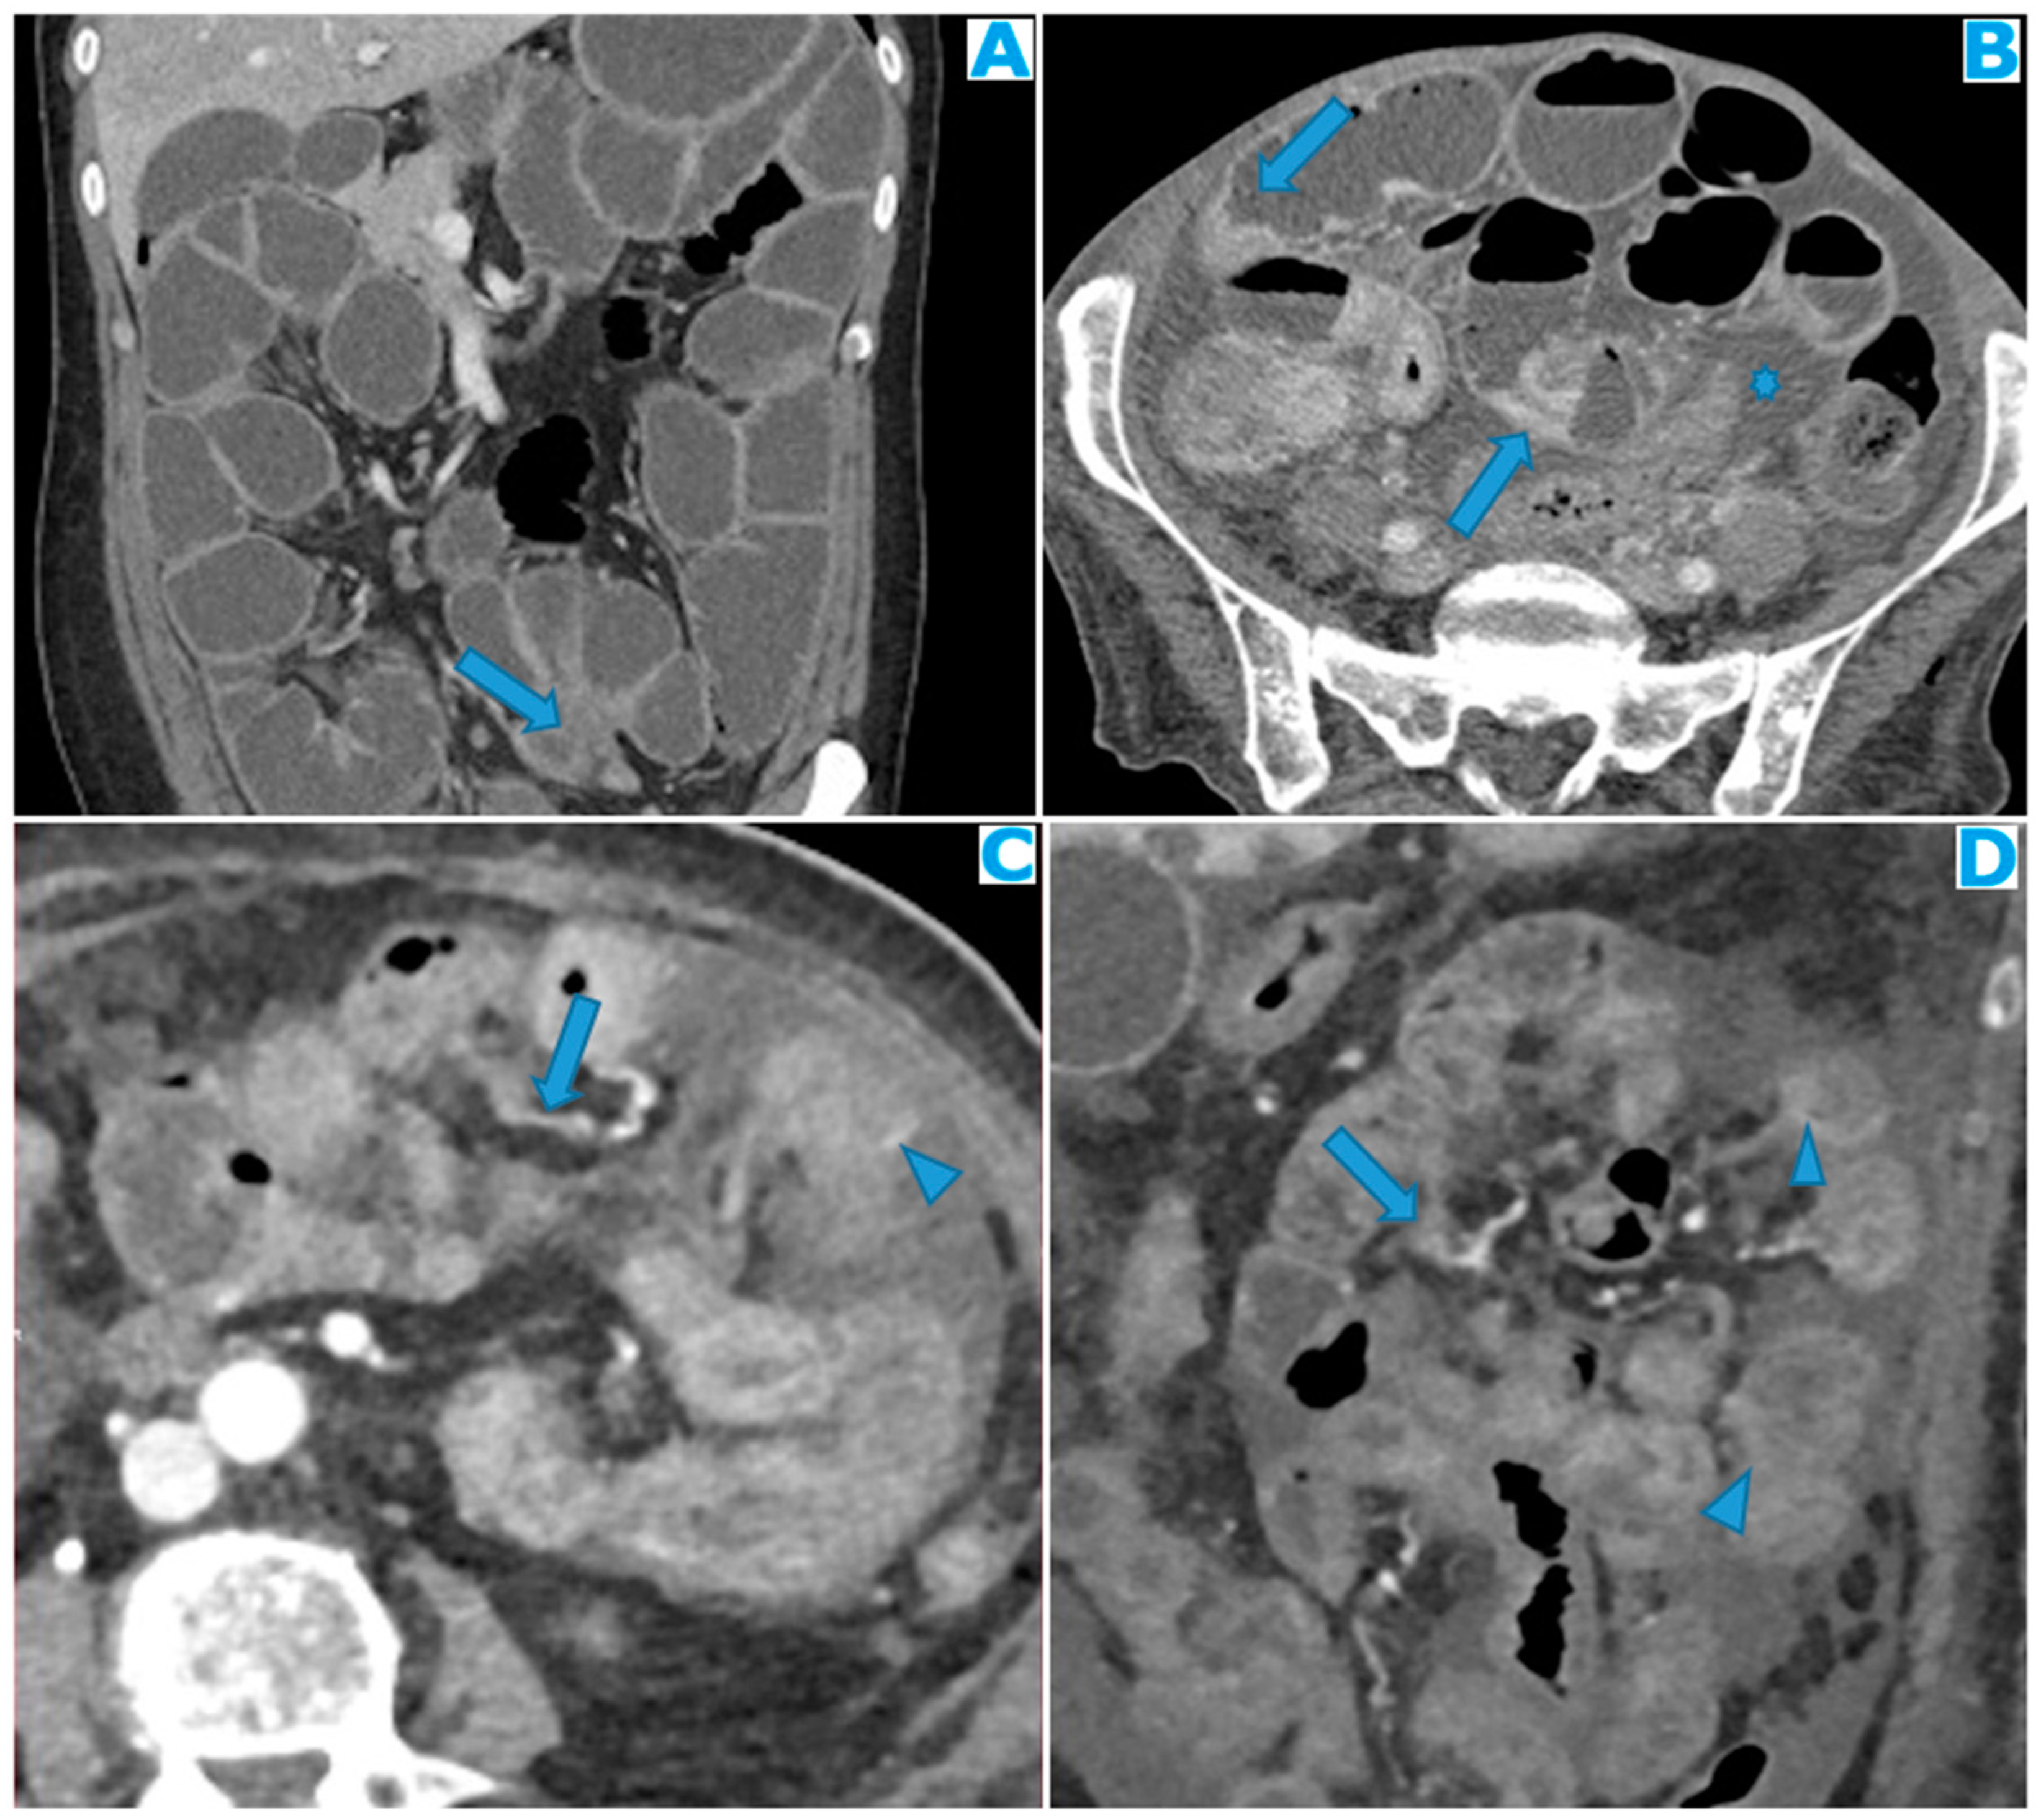

Figure 23.

Axial CE-CT. PC from ovarian carcinoma: mesenteric seeding. Mesenteric involvement may happen as a combination of deposits involving both the mesentery and the bowel serosa, as in this case. Observe the clustered SB loops appearance. The calcified content of some of the deposits enhances their presence (arrow). Omental deposits (*).